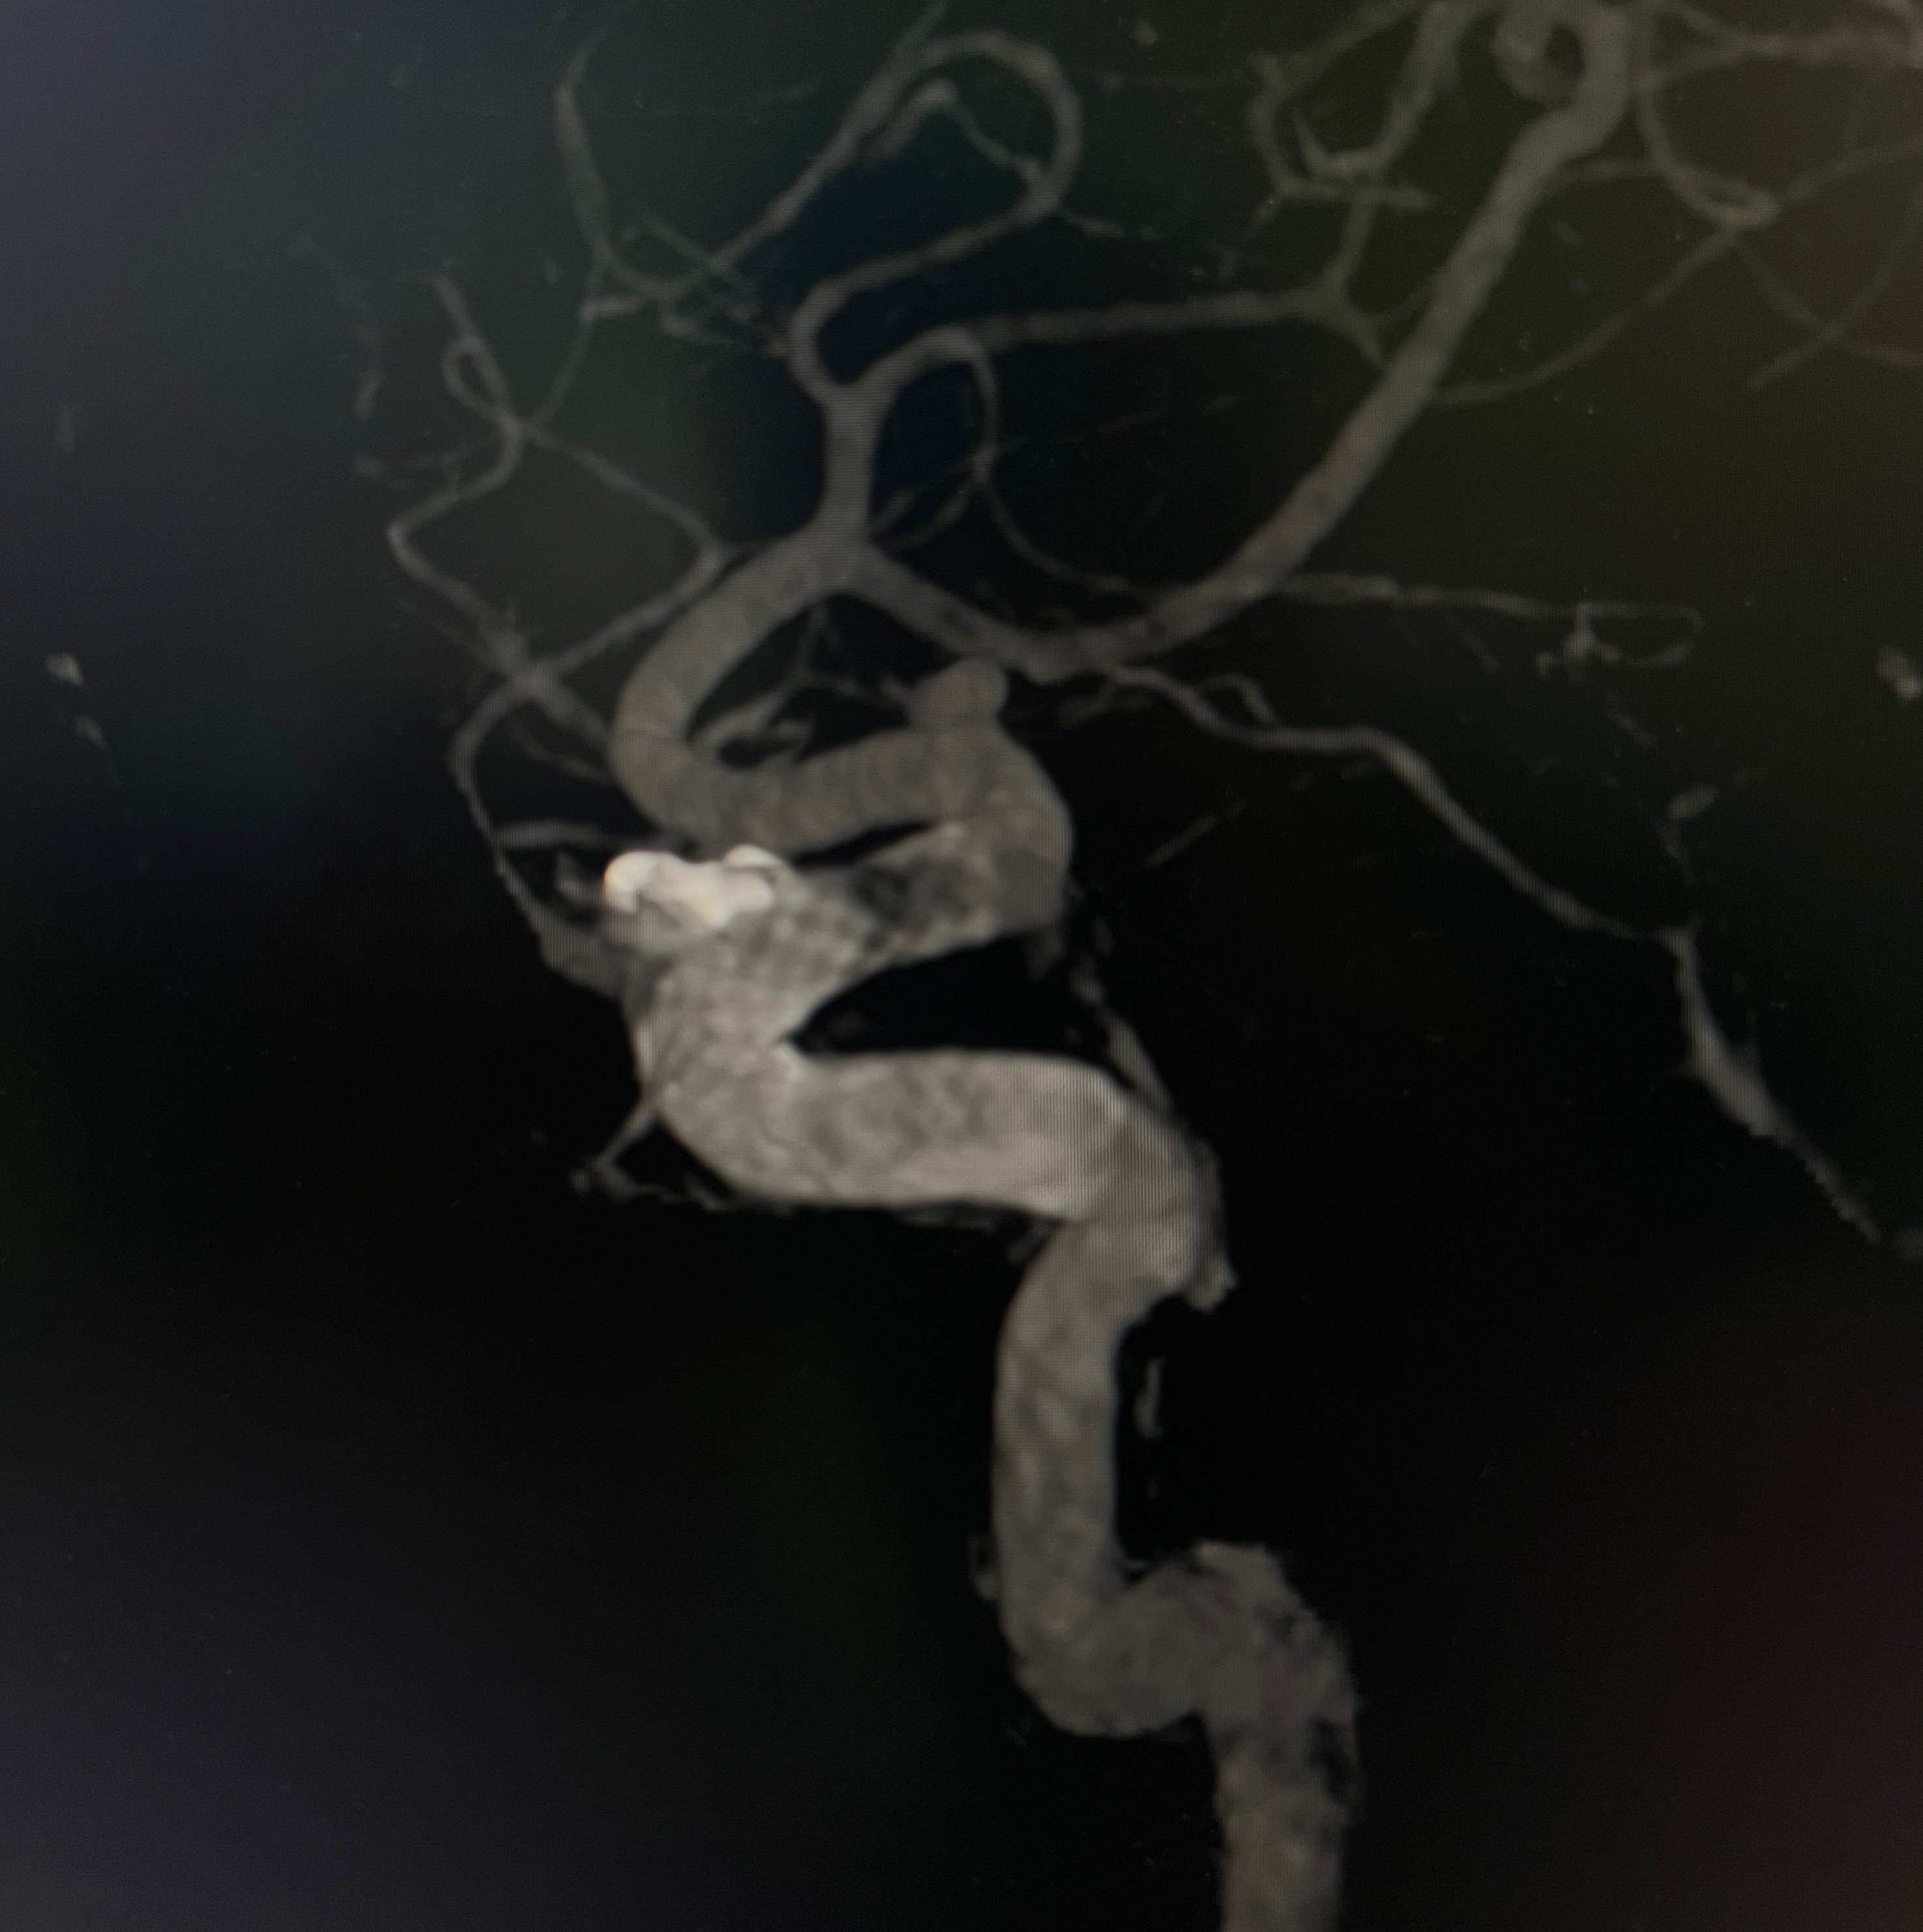

您可能听说过“脑动脉瘤”这个名字,但千万别被它误导了——它并不是我们通常理解的那种会扩散的肿瘤。实际上,它是颅内动脉血管壁上鼓起的一个脆弱“小包”,就像车胎磨损后鼓起的薄弱气囊,是血管壁结构出了问题。这个“小包”的危险性在于它极其脆弱。想象一下,一旦这个气囊破裂,高压的动脉血就会像决堤的洪水一样瞬间涌入大脑周围的腔隙(医学上称为蛛网膜下腔),导致一种非常凶险的急症:蛛网膜下腔出血。这种出血的后果极其严重,被称为“颅内炸弹”毫不为过。统计显示,破裂后约有三分之一的人会不幸丧生;而在幸存者中,很大一部分人会留下严重且持久的神经功能障碍,影响生活能力。更令人担忧的是,如果未能及时得到有效治疗,这个破裂过的“小包”极其容易再次破裂,而每一次破裂都会带来更糟糕的结果。研究发现,大约每50个人中就有1个人可能携带这种潜在的“不定时炸弹”。在大多数情况下,动脉瘤体积较小且深藏在大脑深处,绝大多数人在它破裂前没有任何感觉,常常是在做头部CT血管成像(CTA)或磁共振血管成像(MRA)检查时才被意外发现。那么,身体会给我们发出警告信号吗?在动脉瘤没有破裂时,很多人确实没有任何特殊感觉。但如果这个“小包”长得比较大,压迫到附近的神经,就可能出现一些征兆,比如看东西重影(复视)、一侧眼皮抬不起来(眼皮下垂)或者眼眶后面持续疼痛。而一旦动脉瘤破裂,最典型的信号就是突发的、极其剧烈的头痛,这种痛感常被描述为“一生中最剧烈的头痛”、“仿佛脑袋要炸开”。同时,还可能伴随脖子发硬、恶心呕吐、怕光、意识模糊甚至昏迷。值得庆幸的是,现代医学的发展为我们提供了精确诊断和有效治疗的手段。通过CT血管成像(CTA)或更精确的脑血管造影(DSA),医生可以清晰地看到动脉瘤的位置和形态。治疗的核心目标是在它破裂前或破裂后,将这个危险的“小包”隔离起来,阻止血流继续冲击它。主要方法包括开颅手术用特制的夹子夹闭瘤颈,或者通过微创的介入手术,用弹簧圈或密网支架等材料从血管内部填塞瘤腔或重塑血管。面对脑动脉瘤这个潜在的威胁,“预防胜于治疗”尤为重要。我们能做些什么来降低风险呢?首先,要严格管理好血压,规律监测并按医嘱用药,因为高血压是导致血管壁损伤和动脉瘤形成、破裂的重要推手。其次,坚决戒烟是保护血管健康的关键一步。此外,保持健康的生活习惯,如均衡饮食、适度运动、避免过度劳累和情绪剧烈波动,也对维护血管健康大有裨益。脑动脉瘤虽然像是潜藏在身体里的“不定时炸弹”,但记住关键两点:“未破早干预,破裂急抢救”。掌握这些常识,坚持科学防病,对于有高危因素的人群(如有家族史、长期高血压、吸烟者),在医生建议下进行早期筛查,是守护大脑健康、降低风险最有力的盾牌。

定期体检本是件好事,但如果头部CTA或MRA(磁共振血管成像)的报告单上赫然写着“发现颅内动脉瘤”,难免让人心头一紧,仿佛体内埋下了一颗“不定时炸弹”。此刻,最迫切的问题往往是:这瘤子是不是必须马上手术?别急,答案并非简单的“是”或“否”,而是一个需要医生根据你的具体情况,仔细权衡利弊后做出的个体化决策。核心原则是:并非所有动脉瘤都需要立刻处理!医生做决定的关键,在于评估动脉瘤本身破裂的风险与手术或介入治疗可能带来的风险,哪个更大。这就像是在天平的两端仔细衡量。那么,哪些因素会影响这个决定呢?首先,要看动脉瘤自身的“危险程度”。大小很重要,通常瘤子越大(特别是直径达到或超过7毫米),破裂的风险就越高;而小于3毫米的微小动脉瘤,每年破裂的概率很低,往往可以先观察。位置也很关键,比如位于后循环(如基底动脉尖端、后交通动脉)的动脉瘤,天生就比前循环的更容易破。形态同样值得关注,形状不规则、有“小鼓包”(子瘤)的,比光滑圆形的风险更高。如果在随访观察中发现瘤体在长大,那破裂风险会显著增加,这时通常就建议干预了。其次,患者自身的“个人背景”同样重要。年龄和预期寿命是考量因素,年轻人预期寿命长,即使当前破裂风险不高,但累积一生的风险可能也不小,可能更倾向于处理;高龄患者则需要结合身体状况和整体寿命预期来评估手术风险。健康状况是硬指标,如果有严重的心肺疾病、肾功能不全或凝血障碍等,会增加手术或麻醉的风险,影响决策。既往病史也很关键,如果身体其他部位的动脉瘤曾经破裂过,那么这颗未破的瘤子通常会被视为“高危”,建议积极处理。此外,“三高”控制情况和生活习惯(比如血压控制不佳、仍在吸烟)也会增加破裂风险,进而影响医生的建议。最后,患者的意愿和心理状态也是决策的一部分。即使医生评估风险较低,建议观察,但如果患者因此长期处于极度焦虑状态,严重影响生活质量,那么选择手术干预也可能成为一个合理的理由。基于这些综合评估,可能的处理方案主要有两个方向:一是积极干预治疗,目标是隔绝动脉瘤,阻止血流进入。这主要有两种方法:传统的开颅手术夹闭或者创伤更小的血管内介入治疗。介入治疗常用支架辅助弹簧圈栓塞(在瘤内填塞金属圈)、或者放置密网支架(血流导向装置)或瘤内扰流装置(如WEB),改变血流方向,促使瘤内形成血栓并最终闭塞瘤腔。选择哪种方式,需要经验丰富的神经外科医生,根据动脉瘤的位置、形态、大小以及患者身体状况共同判断。另一个方向是密切影像随访观察。对于破裂风险很低的动脉瘤(比如体积小、形态规则、位置相对安全),或者患者本身健康状况不佳、高龄等情况,医生可能建议定期复查(如每年或隔年做一次CTA或MRA)。这样做的目的是严密监控动脉瘤是否有增大或形态改变,一旦出现变化,再考虑干预也不迟。关键提醒:体检发现脑动脉瘤后,切勿自行判断或恐慌。务必立刻咨询神经外科医生!带上你详细的影像资料和报告,医生会与你充分沟通,详细解释各种方案的利弊、预期效果和潜在风险。这个决策过程没有绝对的“正确答案”,它需要患者、家属与医生共同参与,充分沟通,最终做出最适合个体情况的选择。